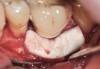

Fig 15. The implant-supported restoration of tooth No. 19 presented with a lack of attached keratinized gingiva, shallow buccal vestibule, and 2 mm of buccal recession.

Figure 15

Fig 16. The restoration exhibited an 8-mm pocket upon probing, with bleeding on the buccal aspect.

Figure 16

Clinical examination showed 2 mm of buccal recession with a shallow vestibule and absence of keratinized attached gingiva against the crown with 8 mm of circumferential pocketing accompanied by bleeding upon probing (Figure 15 and Figure 16). A periapical radiograph showed a symmetrical vertical osseous defect causing the loss of 50% of the bone around the implant (Figure 17). Because the patient had made a significant investment of time and finances to replace her lost tooth with the implant, she desired that the implant and restoration be retained, if feasible.